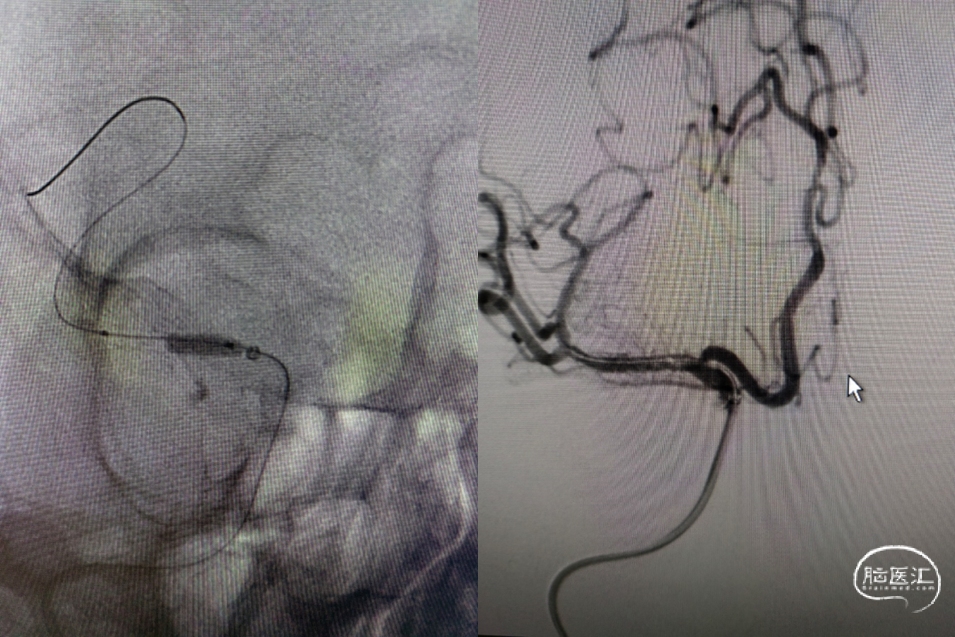

利用赛诺神畅 NOVA DES®颅内药物洗脱支架锚定后释放,血管再通,mTICI 3级,局部动脉给药替罗非班(0.2ug/kg.min)约3ml,持续15分钟。静脉(0.1ug/kg.min)持续泵入24小时后改为口服双抗。